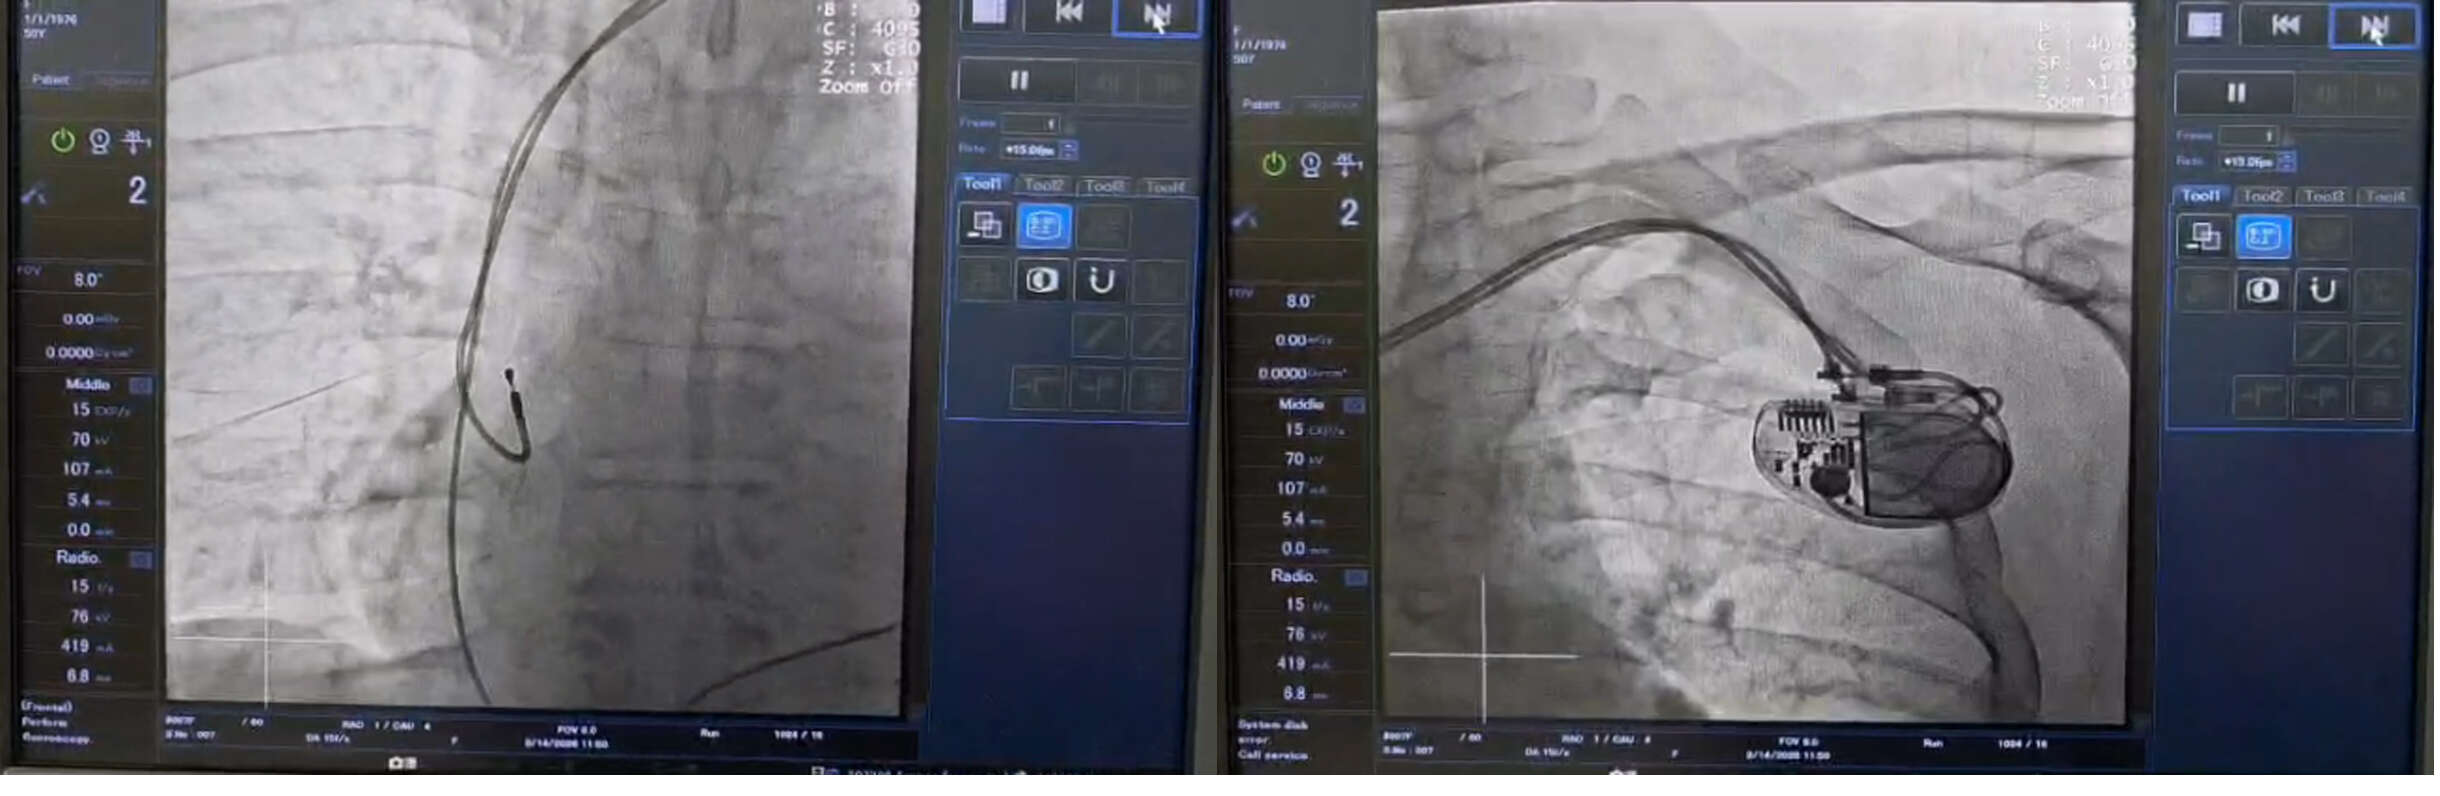

हृदय रोग विशेषज्ञ डॉ. एस.के. त्रिपाठी (DM Cardiology) ने स्थिति की गंभीरता को देखते हुए तत्काल निर्णय लिया। आधुनिक कार्डियक कैथ लैब में किशोरी का पेसमेकर (Pacemaker) प्रत्यारोपण किया गया। यह एक जटिल प्रक्रिया थी, जिसे डॉ. त्रिपाठी और उनकी कुशल टीम ने पूरी सटीकता के साथ अंजाम दिया।

मऊगंज निवासी युवती 'कन्जेनिटल कम्प्लीट हार्ट ब्लॉक' (Congenital Complete Heart Block) जैसी दुर्लभ और घातक स्थिति से पीड़ित थी। जब उसे अस्पताल लाया गया, तो उसकी हालत अत्यंत नाजुक थी। उसे बार-बार बेहोशी आ रही थी और वह कार्डियक अरेस्ट (दिल का दौरा) की स्थिति में थी। ऐसी स्थिति में जीवन बचने की संभावनाएं बहुत कम होती हैं, लेकिन समय रहते विशेषज्ञ डॉक्टरों की निगरानी ने चमत्कार कर दिखाया।